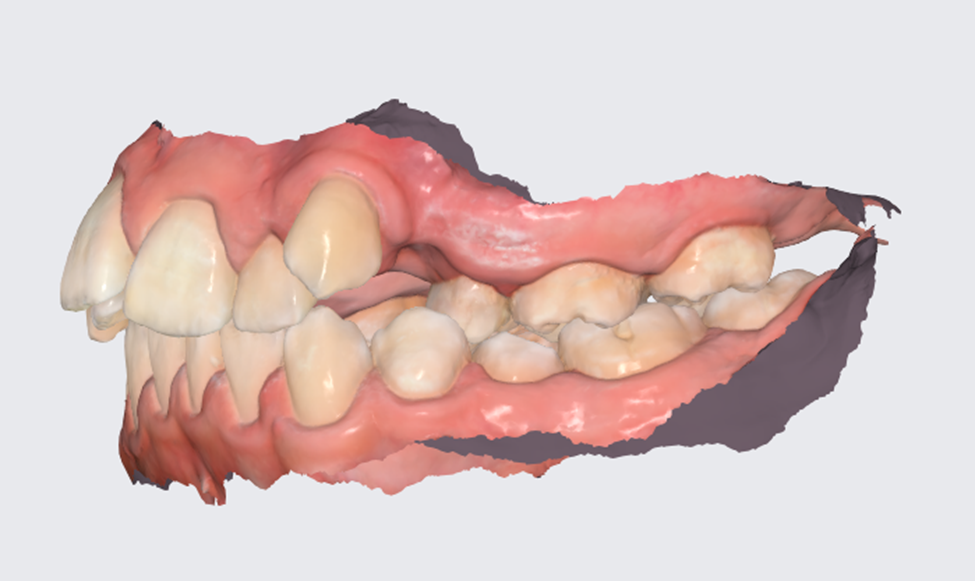

Они самые крайние в зубном ряду и самые последние прорезаются. Чаще всего, зубы мудрости начинают прорезаться, когда уже полностью сформирован постоянный зубной ряд на обеих челюстях, от чего остается критически мало места для полноценного прорезывания и развития восьмых зубов. Именно эта нехватка места и является одним из показаний к удалению зубов. Из-за нехватки места, при активном прорезывании зубов мудрости, ряды сдвигаются, появляется скученность и в боковом и в фронтальном отделах зубных рядов. Восьмерки в данной роли очень коварны, лежат они чаще всего горизонтально или под небольшим углом, и чтобы прорезаться, встать вертикально, им нужно сильно много места для разворота, а такого места совсем нет, поэтому постепенно, под действием 8-к начинают двигаться рядом стоящие зубы к центру, таким образом смещаются и страдают все зубы.

Хуже, если у восьмерок нарушается этап прорезывание. Например, прорезался зуб в сторону щеки, не участвует в жевании, но из-за него часто прикусывается слизистая щеки, от чего происходит частой травме, которая может привести к худшим последствиям. Или же наоборот «ретинированный» зуб,- это значит, что зуб лежит глубоко в кости и не смог прорезаться вообще. В некоторых случаях это может никак не влиять и спокойно пролежать в кости еще долгие годы, но могут и начать со стороны корня разрушать соседние зубы, провоцируя появление кариеса, болезненные воспаления, что приведет так же к подвижности зубов. Поэтому пытаясь переместить зубы с восьмерками по соседству, мы не сможем достичь нужного результата из-за ограничений в движениях.

Поэтому пусть и здоровый зуб мудрости ортодонт рекомендует удалять, так как у данного зуба репутация «бомбы замедленного действия». Пользы в большинстве случаев от 8-х зубов нет, так как в прикус они встают в крайне редких случаях. Конечно, если 8-ка в прикусе и участвует в жевании, здорова и без кариеса, не является причиной сильной скученности ее никто к удалению не порекомендует, но такая ситуация чаще исключение, чем правило.

В большинстве случаев, удаление зубов мудрости, ортодонт рекомендует проводить до начала ортодонтического лечения, ведь это позволит заранее освободить пространство и подготовить челюсть к перемещению зубов. Так же это позволит создать предсказуемые условия для работы брекет-системы или элайнеров.

Когда у пациента сильная скученности и катастрофически нет места для того, чтобы выставить все зубы в ряд как полагается, сохранив при этом качественное смыкание, приходят к компромиссному решению об удалении 4-х зубов.

Таким образом, удаление «здоровых» зубов в ортодонтии никогда не принимается легкомысленно. Есть определённые жалобы пациента, конкретные медицинские показания и рекомендации врача ортодонта по достижению того или иного результата лечения. Оно основано на глубоком анализе клинических ситуаций, рентгеновских снимков, компьютерного моделирования и многолетнего опыта.